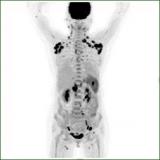

侯露:177Lu标记新型成纤维细胞活化蛋白抑制剂靶向治疗放射性碘难治性分化型甲状腺癌的初步研究

放射性示踪剂[68Ga] Ga-DOTA.SA.FAPi在转移病灶明显浓聚,同时口腔粘膜、唾液腺、肝脏、胰腺、胆囊、结肠和肾脏存在一定的生理性摄取。使用[177Lu]Lu-DOTAGA.(SA.FAPi)2治疗后直到第168h仍可见主要病灶的放射性浓聚。患者治疗前后出现了明显的分子反应,PET/CT显示主要病灶的大小和SUVmax都有减小和降低,患者的Tg水平也从>300000 ng/mL下降到6586,达到了显著的生化反应;该患者治疗前后VASmax评分也从10分下降到4分,临床症状得到明显的缓解。 2022-09-25 靶向治疗放射诊疗